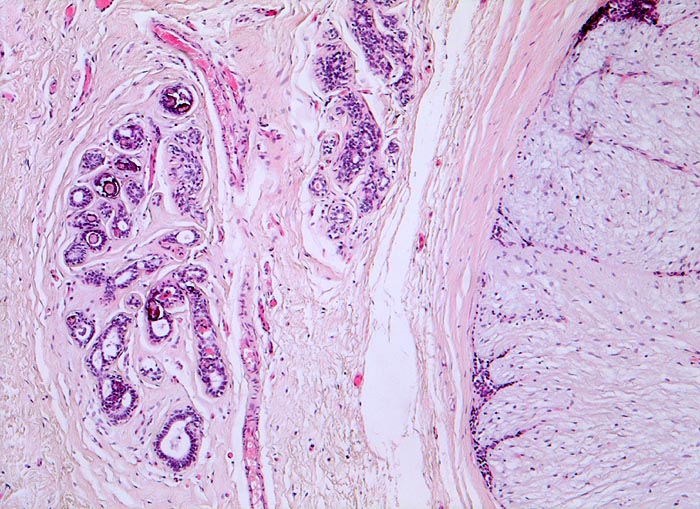

Morphologische Merkmale:

• Zwei scharf begrenzte Tumorknoten.

• Biphasischer organoid aufgebauter Tumor bestehend aus kompaktem zellarmem fibroblastärem Stroma, das in konzentrischen Lamellen um verzweigte, miteinander anastomosierende Drüsenschläuche angeordnet ist.

• Die Drüsenschläuche werden durch das Stroma komprimiert.

• Das Stroma erscheint herdförmig bläulich und aufgelockert durch Muzineinlagerungen.

• Stellenweise gewöhnliche intraduktale Epithelproliferation ohne Atypie.

• Die Drüsen werden ausgekleidet von einer inneren kubischen bis hochprismatischen Zellschicht und einer äusseren abgeflachten Myoepithelschicht mit klarem Zytoplasma.